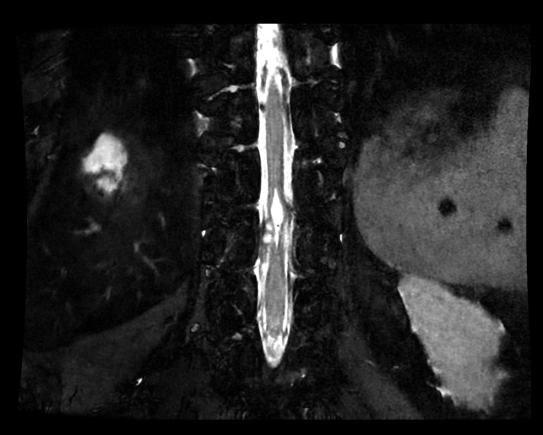

胸椎常规+增强MRI:约T10~11水平胸髓腹侧异常信号,不除外占位性病变,不伴强化(图2)。

脊髓3D MRI:T10~T11处囊肿有3处,大者位于脊髓腹侧,两小者位于囊肿右前下方髓外脊膜或脉络丛可能,有粘连(图3)。

image.png

图2 胸椎常规+增强MRI:约T10~11水平胸髓腹侧异常信号,不除外占位性病变,不伴强化。

图3 脊髓3D MRI:T10~11处囊肿有3处,大者位于脊髓腹侧,两小者位于囊肿右前下方髓外脊膜或脉络丛可能,有粘连。